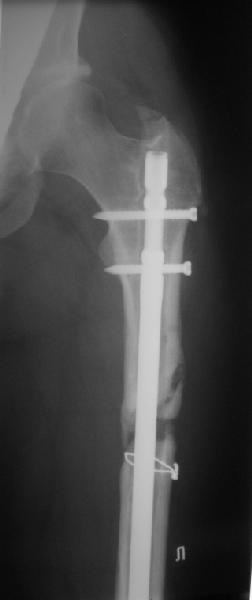

фото несращения бедра